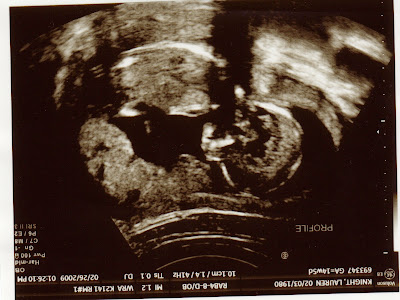

It’s Alive! And Upside Down!

NewBaby has been quite elusive, evading all attempts to find fetal heart tones, and laying low (literally) enough that I didn’t even feel pregnant. But it is now safe to say, at 15 weeks, NewBaby is doing well and will most likely stick around after all! Above is a picture of the profile, upside down (sorry, I’m just not that technologically saavy so take it or leave it). For those of you who don’t look at these pictures very often, the head is down on the lower right corner, with the face looking into the lower left corner. The body is a blur in this one, but the sonographer said as far as she could tell everything looks normal. We will find out more, including the sex of the baby (YAY!) in about a month, at the end of March.